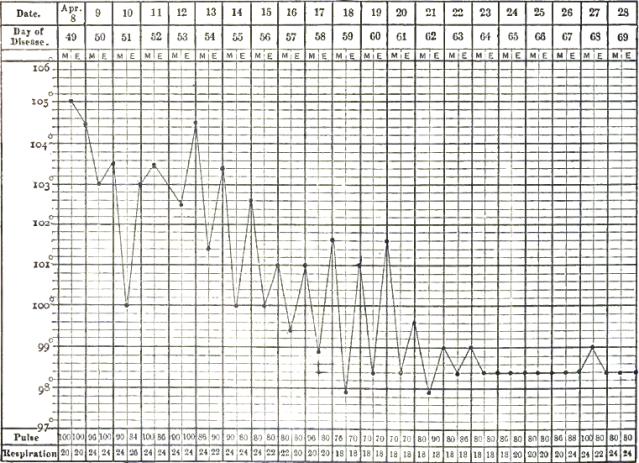

| 13. | CHART SHOWING RECRUDESCENCE OF FEVER FROM INDISCRETION OF DIET |

| 14. | CHART SHOWING FALL OF TEMPERATURE FROM INTESTINAL HEMORRHAGE IN TYPHOID FEVER |

| 15. | PULSE-TRACING IN RELAPSES OF TYPHOID FEVER |

| 16. | CHART OF TEMPERATURE IN TYPHOID FEVER WITH RELAPSE.—ORIGINAL ATTACK |

| 17. | CHART OF TEMPERATURE IN TYPHOID FEVER WITH RELAPSE.—RELAPSE |

| 18. | TEMPERATURE CHART OF TYPHOID FEVER.—ABORTIVE ATTACK, FOLLOWED BY TYPICAL ATTACK |